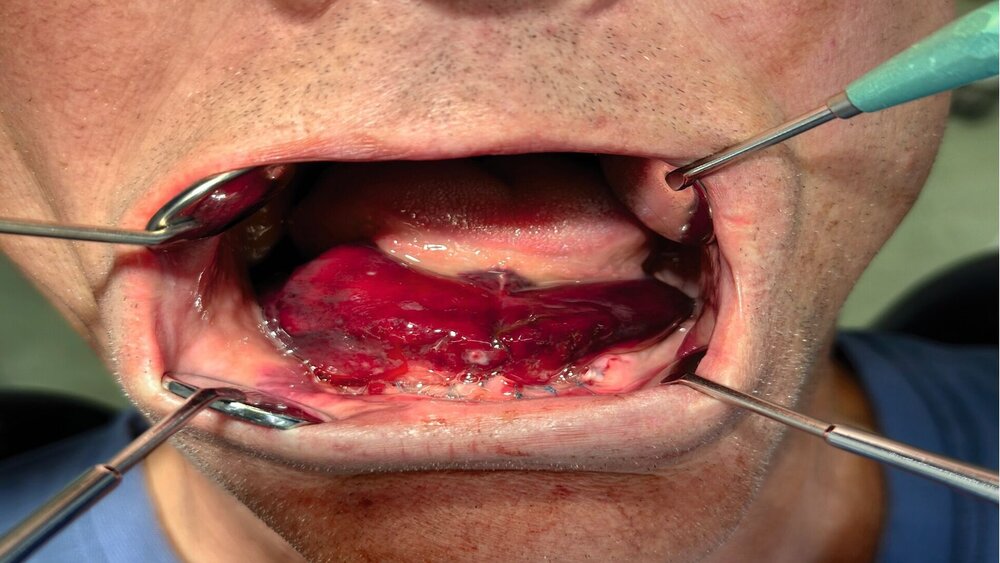

Anamnestisch bestand eine ASS-Dauertherapie nach mehrfacher Stentimplantation bei einer vorbestehenden Koronaren Herz-Kreislauf-Erkrankung und anamnestisch berichteten Herzinfarkten in den Jahren 2013, 2017 und 2020, eine arterielle Hypertonie sowie eine Hyperlipoproteinämie. Im Rahmen der notfallmäßigen Erstvorstellung zeigte sich in der klinischen Untersuchung intraoral ein ausgedehntes und schmerzhaftes Hämatom des vorderen Mundbodens (Abbildung 1), das die Zunge deutlich Richtung Oropharynx verdrängte und den Patienten beim Schluckakt behinderte. Eine Dyspnoe bestand zum Zeitpunkt der Erstuntersuchung nicht.

Therapeutisch erfolgten als abschwellende Maßnahmen die Applikation von lokaler Kälte sowie die Gabe von Dexamethason für insgesamt drei Tage (8 mg – 8 mg – 8 mg; 4 mg – 4 mg – 4 mg; 2 mg – 2 mg – 2 mg). Des Weiteren erhielt der Patient eine intravenöse Antibiose zur Infektionsprophylaxe mittels Sultamicillin (3 x 3 g/d für vier Tage) sowie für weitere drei Tage peroral mittels Amoxicillin/Clavulansäure (875/125 mg 2 x 1 Tablette/d). Ergänzend erfolgten eine adaptierte orale Schmerztherapie mittels Metamizol (3 x 30 gtt/d), die Umstellung auf flüssige Kost sowie tägliche Wundkontrollen und Reinigungen mittels Chlorhexamed-Mundspüllösung 0,2 Prozent. Darunter zeigten sich ein rascher Rückgang des Hämatoms und eine zeitgerechte Abheilung der Implantatinsertionsstellen im weiteren stationären Verlauf (Abbildung 4), sodass der Patienten nach viertägiger Überwachung mit einer geringen Restschwellung / einem geringen Resthämatom und ohne klinische Beschwerden in die ambulante Nachsorge entlassen werden konnten (Abbildung 5). Während der ambulanten Nachkontrollen zeigte sich eine vollständige Regression der Beschwerden.